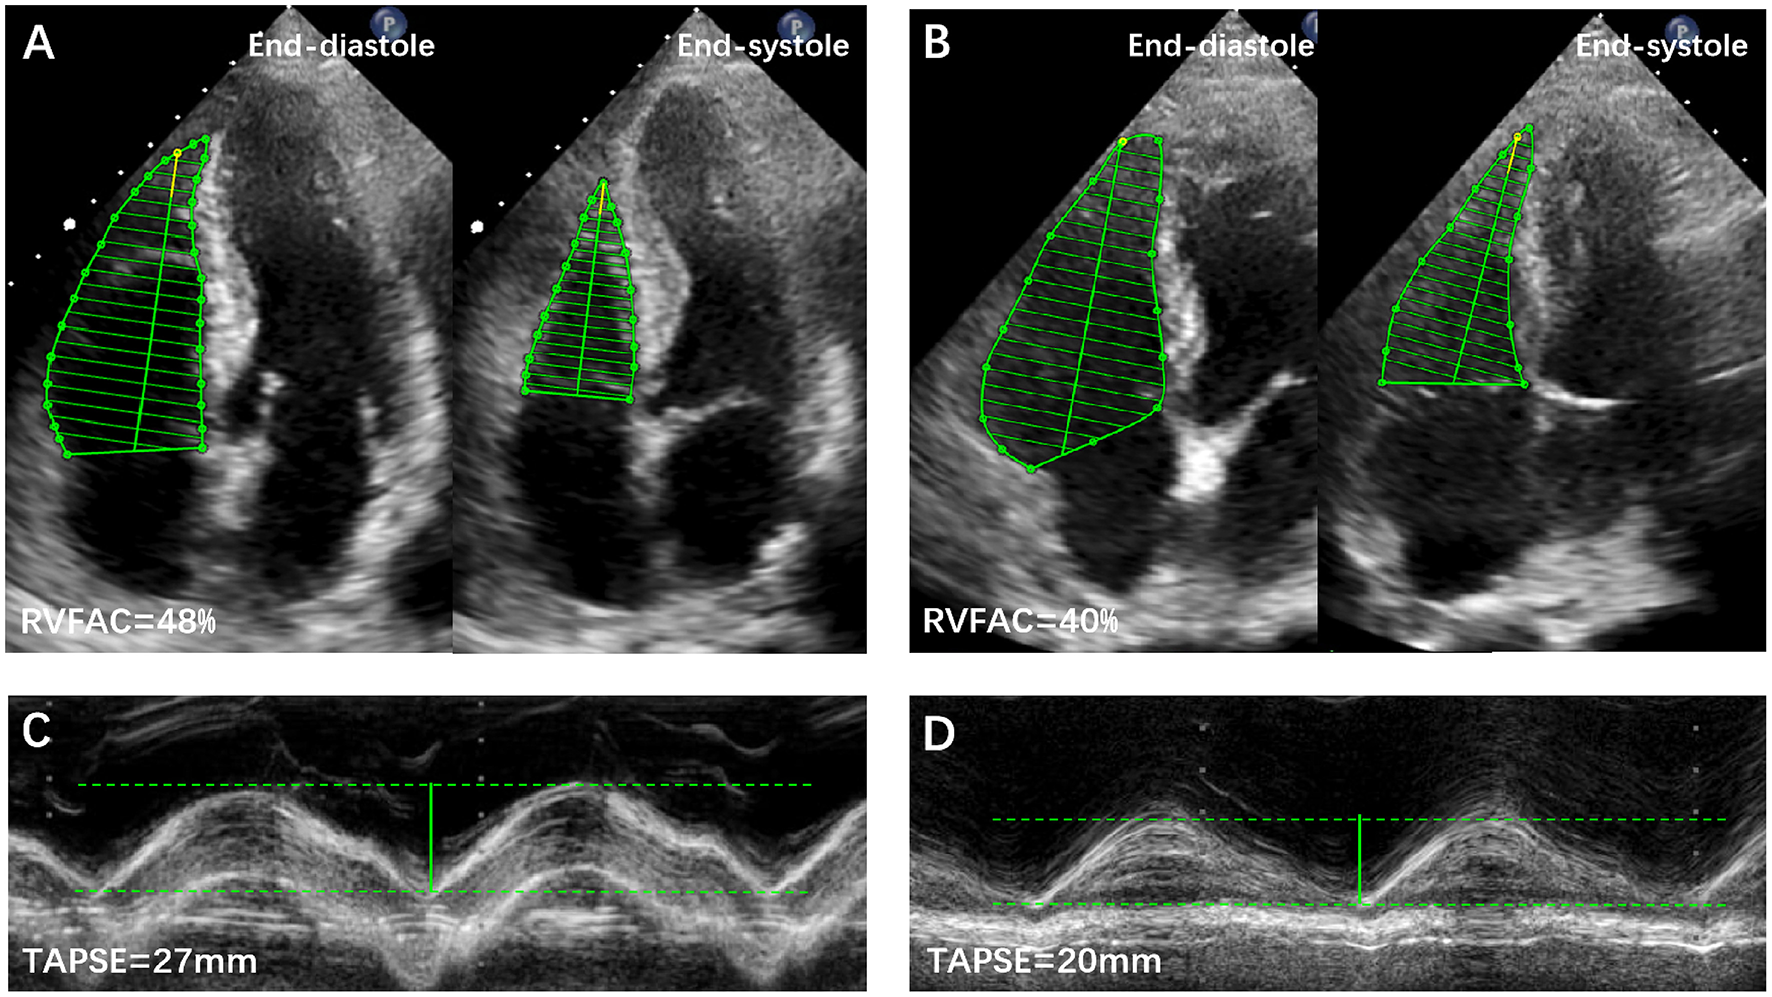

RV function was assessed by tricuspid annular plane systolic excursion (TAPSE), fractional area change (FAC), peak systolic velocity (S′) of the tricuspid lateral annulus, and myocardial performance index (MPI) (9). RV dysfunction was defined as the aforementioned parameters measured to be lower than the published reference values (9). Representative examples of RVFAC and TAPSE measurements from COVID-19 patients without and with CVD are shown in Figure 1. The degree of tricuspid regurgitation (TR) was defined as moderate, moderate to severe, or severe TR. Pulmonary artery systolic pressure (PASP) was estimated according to published guidelines (9).

Figure 1

Representative examples of RVFAC and TAPSE measurements from COVID-19 Patients without and with CVD. (A) RVFAC in COVID-19 patient without CVD. (B) RVFAC in COVID-19 patient with CVD. (C) TAPSE in COVID-19 patient without CVD. (D) TAPSE in COVID-19 patient with CVD. CVD, cardiovascular disease; RVFAC, right ventricular fractional area change; TAPSE, tricuspid annular plane systolic excursion.